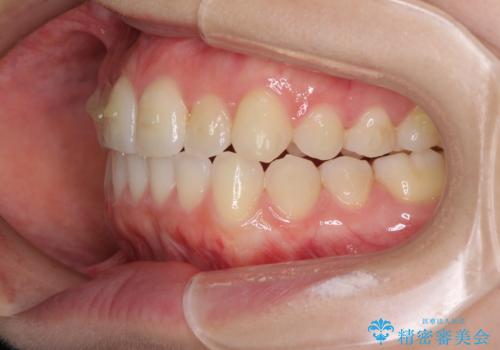

前歯のクロスバイトをインビザライン矯正で改善

- 前歯のデコボコと上下のクロスバイトを気にして来院された患者様です。

インビザラインを用い、IPR(歯と歯の間を削る)と歯列全体を拡大させることで、歯並びを整えていくこととしました。

上の前歯が下の前歯を乗り越える際、奥歯がほとんど咬めない時期があり、乗り越えた後も、インビザライン特有の奥歯の咬みにくさが続きました。

咬み合わせ改善のために治療期間を要しましたが、最終的に奥歯はしっかりと咬めるようになりました。